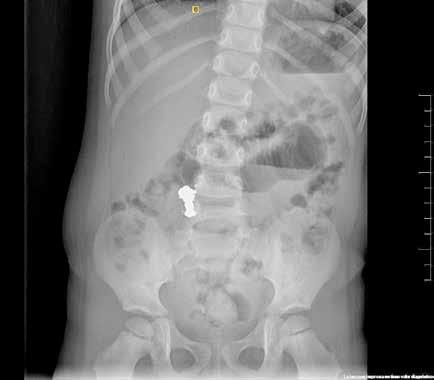

Paciente varón de 6 años sin antecedentes de interés, que acudió al Ser vicio de Urgencias 5 horas (h) después de sufrir un trauma contuso en hipogastrio con el manillar de la bicicleta. El paciente presentaba buen estado general y constantes vitales normales pero refería dolor abdominal genera lizado y continuo, sin otros síntomas acompañantes. En la inspección abdo minal se observó una lesión eritematosa-equimótica de aproximadamente 3x3 cm en hipogastrio, levemente dolorosa pero sin alteraciones subyacen tes (Figura 1). El abdomen era blando, depresible y doloroso a la palpación profunda pero sin defensa ni signos de irritación peritoneal. En la analítica sanguínea (AS) se documentó una hemoglobina de 13.5 g/dL, sin elevación de enzimas hepáticas ni pancreáticas, el uroanálisis también fue normal. Se realizó una ecografía de abdomen en la que se visualizaban pequeñas lengüetas de líquido libre intraabdominal y focos de hiperecogenicidad de la grasa mesentérica con engrosamiento focal del peritoneo. Se completó el estudio con una tomografía axial computarizada (TAC) abdominopélvica con contraste que identificó escasa cantidad de líquido libre perihepático e interasas con leve distensión de asas ileales, sin observar otras lesiones. Todo lo anterior sugestivo de contusión mesentérica por lo que se decidió

Debido al empeoramiento clínico se solicitó una ecografía de abdomen durante la cual estuvo presente el equipo tratante y en la que se evidenció aumento del líquido libre de aspecto ecogénico sin otras alteraciones. Sin embargo, ante la evolución tórpida y la localización de la contusión abdo minal se comunicó al radiólogo la posibilidad de una perforación intestinal, quien realizó una segunda exploración ecográfica enfocada en las zonas cefálicas y anteriores del abdomen en las que se ubicaría el aire, entonces se visualizaron artefactos en la superficie hepática que sugerían burbujas aéreasextraluminales (Figura 2A). Se realizó una radiografía toracoabdomi nal (RxTA) que confirmó la presencia de neumoperitoneo subdiafragmático bilateral (Figura 2B).

Las principales herramientas diagnósticas ante la sospecha de perfora ción intestinal son la RxTA, la ecografía y la TAC. El estudio radiológico ha de empezar por la ecografía y posteriormente la TAC, para descartar lesiones más comunes como las hepáticas y esplénicas. Si entonces no se ha visualizado neumoperitoneo y persiste la sospecha de perforación, debe realizarse una RxTA (3). El aire libre se identifica más frecuentemente en la región anterior del abdomen y perihepático, como en nuestro caso. La ecografía además der ser la primera prueba a realizar, es una buena opción en el control evolutivo de lesiones menores. Sus principales ventajas son el bajo costo, amplia disponibilidad y ausencia de radiación, con el inconve niente de la dependencia del observador (8). Respecto a la RxTA, la tasa de visualización de aire libre subdiafragmático en la perforación de víscera hueca es del 18-57%, por ello el complemento con otra serie de imágenes diagnósticas, como la TAC, puede ser necesario (3). Los principales hallaz gos tomográficos que sugieren lesión del TGI son el aire extraluminal, extravasación de contraste, líquido libre intraperitoneal, infiltración en la raíz del mesenterio, entre otros (2).

Figura 2. Ecografía con burbujas aéreas extraluminales en la superficie hepática sugestivas de neumoperitoneo (A, flechas). RxTA con neumoperitoneo subdiafragmático bilateral (B, flechas).